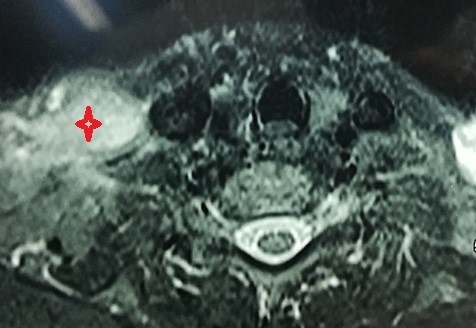

Transverse view of magnetic resonance imaging with dye showing in red a tumor of the right cervical nerve plexus at the outlet of the neck of a 38-year-old woman.